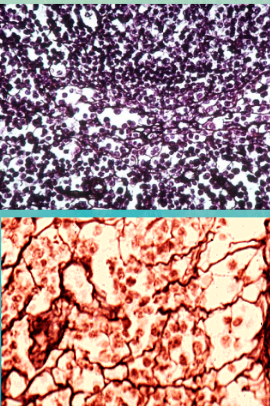

reticular connective tissue

Consists of a delicate network of reticular fibers

Forms the stroma or internal supporting network in lymph organs

blood

blood: erythrocytes (red blood cells)

Anucleated made in bone marrow

Hemoglobin carries oxygen

blood: leukocytes (white blood cells)

Larger and nucleated

5 types (3 made in bone marrow and 2 in lymph)

Phagocytize bacteria

blood: thrombocytes (platelets)

Smallest

Function in coagulation